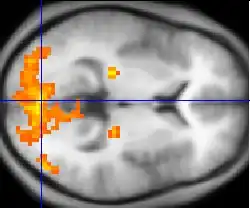

Нейровизуализация с помощью аппаратуры фМРТ и ПЭТ работы мозга при шизофрении указывает на функциональные отличия, затрагивающие чаще всего фронтальные и височные доли, а также гиппокамп[139]. Эти отличия связывают с нейрокогнитивными нарушениями, часто отмечаемыми при шизофрении[140], однако трудно отделить возможный вклад в эти нарушения, связанный с антипсихотическими препаратами, которыми лечились почти все пациенты, принимавшие участие в исследованиях[141]. У больных шизофренией также обнаруживается гипофронтальность — уменьшение притока крови к префронтальным и лобным отделам коры головного мозга[142][143].